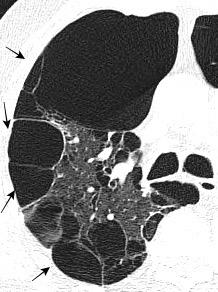

PATRÓN DE PANALIZACIÓN.

Múltiples espacios “quístico”

Habitualmente en bases y Áreas laterales

Neumonía Interst. Usual

(Fibrosis idiopática)

Enf. colágeno (AR, etc.)

Fibrosis por drogas

Asbestosis

Honey comb pattern

Estadio final de Neumonitis de hipersensibilidad

Sarcoidosis

Distrés Resp. Agudo

Radiación

Neumonía interst. no específica (NINE)

Neumonía intersticial usual Webb. 2005/ Hansell DM. Radiology